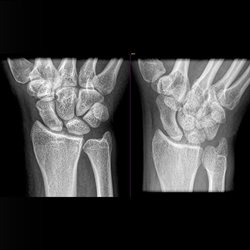

Various adult extremity cases. Shoulder, wrist, ankle, elbow.